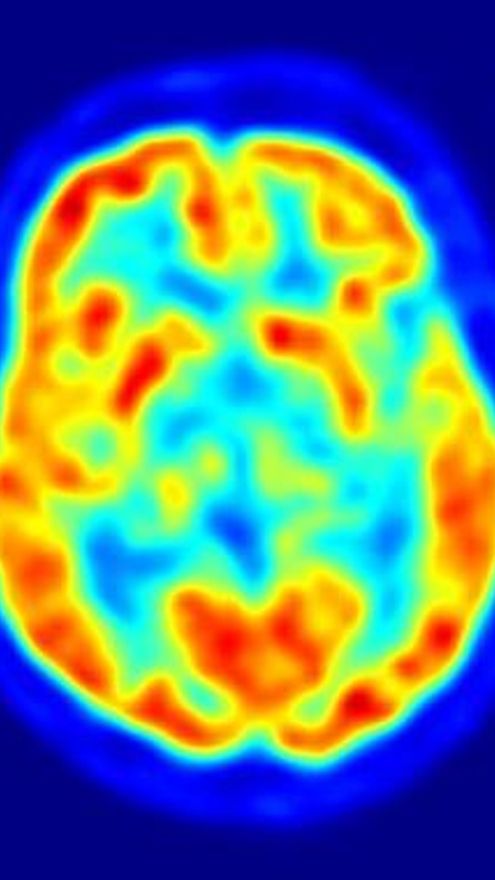

Los científicos del Instituto Allen para la Ciencia del Cerebro han publicado, en el último número de la revista 'Nature', los primeros datos del análisis del atlas Allen del Cerebro Humano, el primer análisis profundo y a gran escala del cerebro humano. Entre otro datos, muestra que hasta 84 por ciento de todos los genes se expresan, o se enciende, en algún lugar en el cerebro humano.

El trabajo analiza específicamente todos los genes y estructuras activas del cerebro, así se ofrecen datos de perfiles de 400 a 500 áreas cerebrales de los distintos hemisferios utilizando la tecnología de 'microarrays' y consta de más de 100 millones de mediciones de expresión génica que abarcan tres cerebros humanos individuales hasta la fecha.

Entre otros hallazgos, estos datos muestran que 84% de todos los genes se expresan en algún lugar en el cerebro humano y en los patrones que son sustancialmente similares de un cerebro a la siguiente.

Según informa, individualmente los cerebros humanos comparten el mismo modelo básico molecular, y un análisis más profundo de esta arquitectura compartida revela, entre otras cosas, que las regiones vecinas de la corteza del cerebro son bioquímicamente más similares entre sí que a las regiones del cerebro más distantes, lo que tiene implicaciones para la comprensión del desarrollo del cerebro humano, tanto durante el tiempo de vida ya lo largo de la evolución.

Por otra parte, se puede observar que los hemisferios derecho e izquierdo no muestran diferencias significativas en la arquitectura molecular. Esto sugiere que las funciones tales como la lengua, que generalmente son manejados por un lado del cerebro, probablemente resultan de diferencias más sutiles entre los hemisferios.

“A pesar de controlar una variedad de funciones, que van desde la percepción visual para la planificación y resolución de problemas, la corteza es muy homogénea en relación a otras regiones del cerebro. Esto sugiere que los mismos elementos funcionales básicos se utilizan en toda la corteza y que la comprensión de cómo se trabaja la zona al detalle va a descubrir los fundamentos que se aplican a las otras áreas, también”, añaden los investigadores.